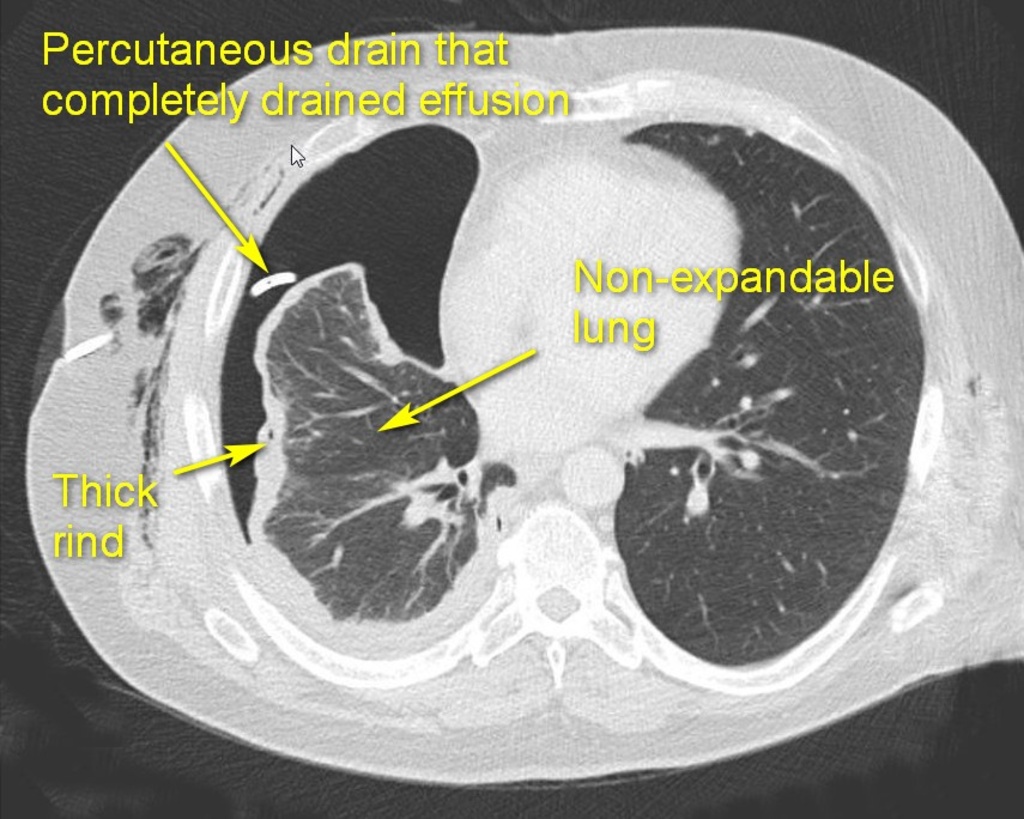

The fibrous phase (Stage III) is best avoided by NOT DELAYING drainage during the earlier stages. This phase starts in 4-6 weeks and is characterized by the formation of a thick, fibrous rind (peel or cortex) on the visceral pleural surface of the lung. This peel traps the compressed lung, serving as a non-expandable “cast.” The lung may become densely adherent to the chest wall and diaphragm (particularly posterior-inferiorly). Parietal pleura becomes fibrotic as well, resulting in intercostal spaces construction and limiting chest wall mobility. Development of this fibrotic process in the chest is called fibrothorax. Even after drainage of the effusion the lung cannot appropriately expand (trapped lung). A thoracotomy and open decortication are usually required to achieve a complete decortication and reexpand the lung.

- Presence of discrete pleural rind predicts the likely failure of tube management and need to perform an operation. Lower thickness of pleural rind predicts the success of VATS decortication.